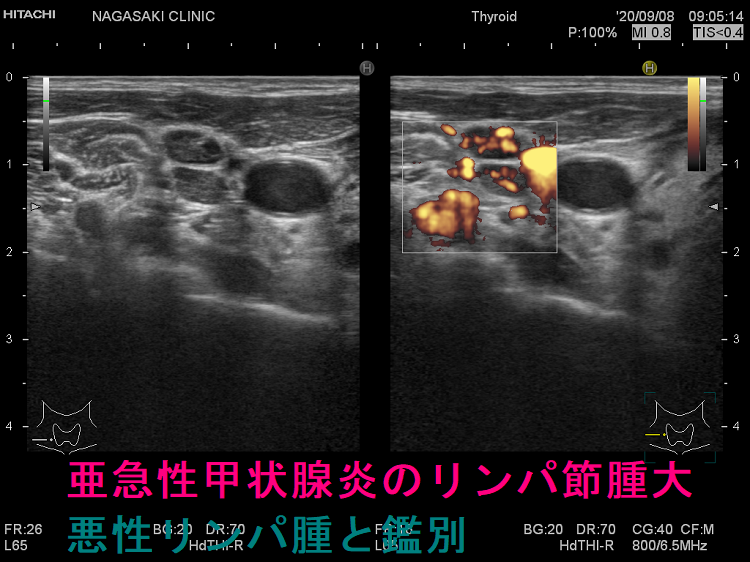

亜急性甲状腺炎のリンパ節腫大を悪性リンパ腫と間違えない

亜急性甲状腺炎の頚部リンパ節腫大が悪性リンパ腫の様に見える場合があります。甲状腺内の低エコー領域も甲状腺悪性リンパ腫との鑑別が必要なので、益々紛らわしくなります。